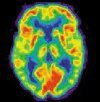

ПЭТ-КТ головного мозга

ПЭТ-КТ головного мозга. Современный метод исследования с использованием специальных радиофармпрепаратов для получения информации о функциональном состоянии различных частей мозга. В то время как МРТ и КТ используются для изучения анатомической структуры мозговой ткани, ПЭТ-КТ используется для оценки ее функциональной активности и поэтому называется функциональной томографией. Таким образом, позитронно-эмиссионная томография является качественно новым методом диагностики, благодаря которому диагностика заболеваний стала возможной в самом начале ее развития, до появления морфологических изменений.